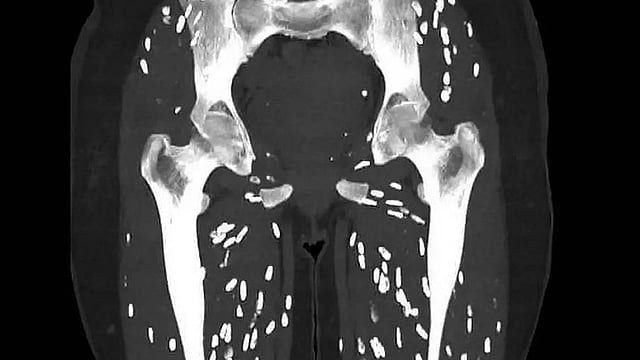

കാലുകളിൽ ​ഗുരുതരമായി ഇൻഫെക്ഷൻ വ്യാപിച്ചത്തിന്റെ ഞെട്ടിക്കുന്ന ചിത്രം

വേവിക്കാത്ത പന്നിയിറച്ചി കഴിച്ചതിന് പിന്നാലെ ​ഗുരുതര പാരസൈറ്റ് ഇൻഫെക്ഷൻ ബാധിച്ച രോ​ഗിയുടെ സിടി സ്കാൻ പങ്കുവെച്ച് ഡോക്ടർ. കാലുകളിൽ ​ഗുരുതരമായി ഇൻഫെക്ഷൻ വ്യാപിച്ചത്തിന്റെ ഞെട്ടിക്കുന്ന ചിത്രമാണ് ഫ്ലോറി‍ഡ‍ എമർജൻസി ഡിപ്പാർട്മെന്റിലെ ഫിസിഷൻ ഡോ. സാം ​ഗാലിയാണ് എക്സിലൂടെ പങ്കുവെച്ചത്.

ഇതുവരെ കണ്ടെതിൽ വെച്ച് ഏറ്റവും ഭീകരമായ സിടി സ്കാൻ, ഇത് എന്ത് രോ​ഗമാണെന്ന് മനസിലായോ എന്ന അടിക്കുറുപ്പോടെയാണ് ഡോക്ടർ ചിത്രം പങ്കുവെച്ചിരിക്കുന്നത്. സിസ്റ്റിസിർകോസിസ് എന്ന പാരസൈറ്റ് ഇൻഫെക്ഷനാണ് ഇതെന്നും പിന്നീട് ഡോക്ടർ കമന്റിൽ വ്യക്തമാക്കുന്നുണ്ട്. ടീനിയ സോലിയം എന്ന നാടവിരയുടെ മുട്ടയിൽ നിന്നാണ് ഈ അണുബാധ ഉണ്ടാകുന്നത്. പന്നികളിൽ കാണപ്പെടുന്ന നാടവിരയിലെ ലാർവൽ സിസ്റ്റുകൾ ഇറച്ചി നന്നായി വേവിക്കാത്തതു മൂലം ശരീരത്തിൽ എത്തുകയും. അണുബാധയ്ക്ക് കാരണമാവുകയും ചെയ്യുന്നു.